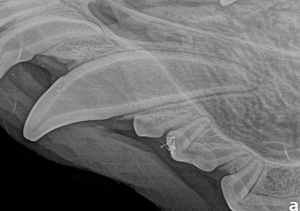

Canine Full Mouth Radiograph Example